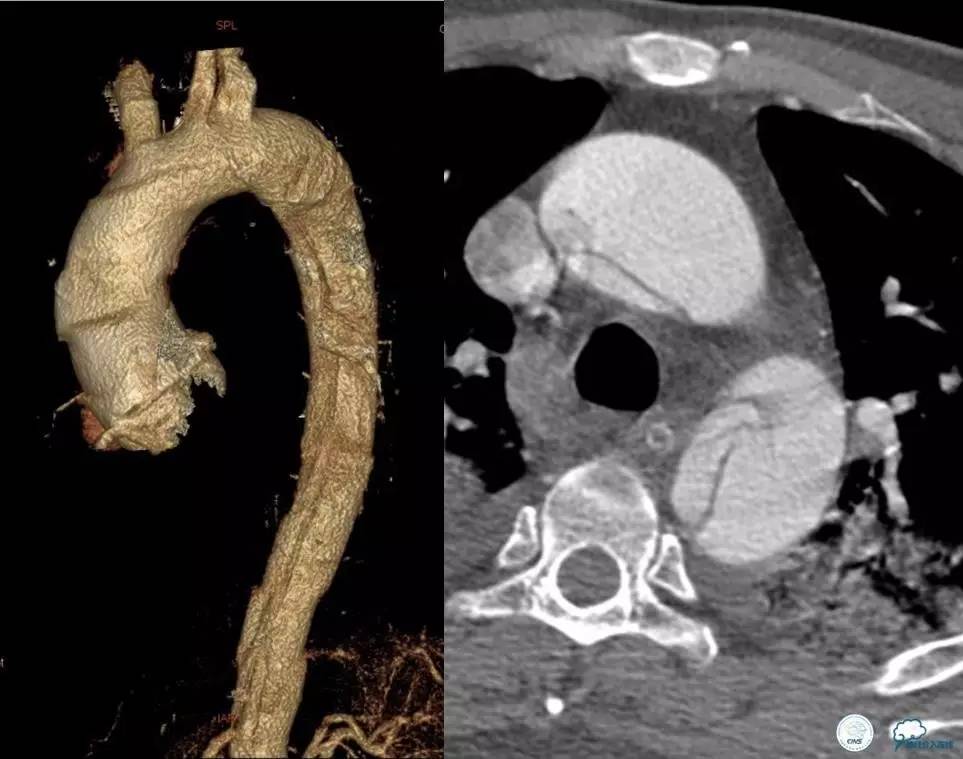

▼主动脉全程CT

诊断:

主动脉夹层 DeBakey Ⅰ型

短暂性脑缺血发作

急性心肌缺血

急性肾功能不全

急性肠系膜动脉缺血

中间诊断:

主动脉夹层 De Bakey Ⅰ型